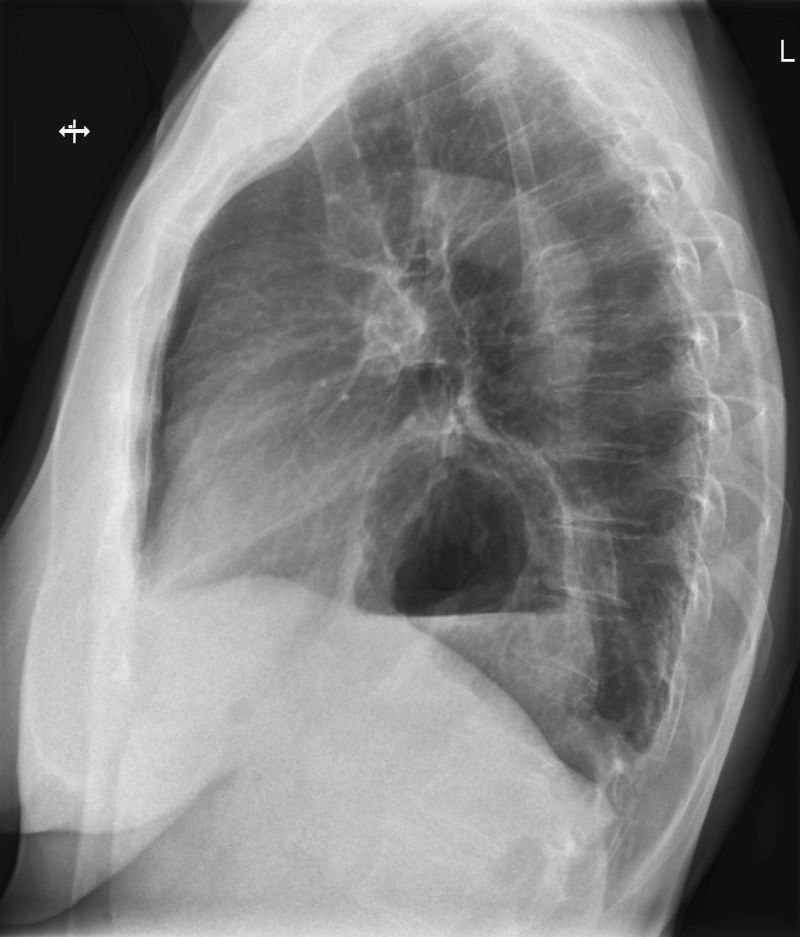

Röntgen der Lunge

Die Röntgenaufnahme der Lunge wird typischer Weise im Stehen am Wandstativ in zwei Ebenen in der Regel unter tiefer Einatmung durchgeführt. So können Veränderungen in der Lunge festgestellt und lokalisiert werden wie z.B. Tumoren, Lungenentzündung, Belüftungsprobleme von Lungenabschnitten und etliche andere Erkrankungen.